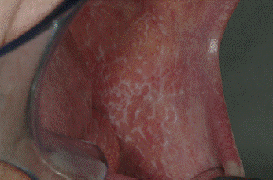

ORAL LICHEN PLANUS

RETICULAR LICHEN PLANUS